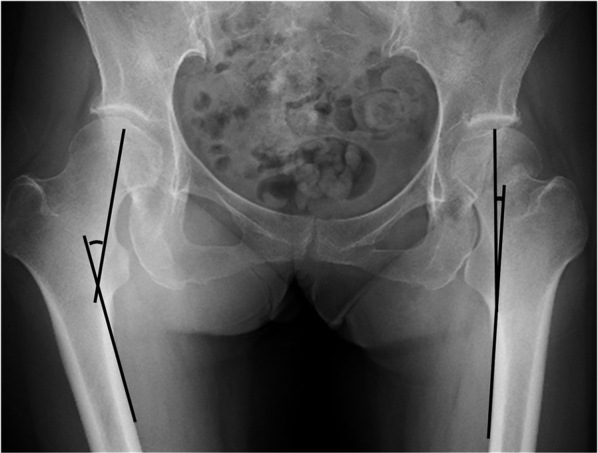

The objective of this study was to evaluate and compare the clinical and radiographic outcomes between in situ fixation and fixation after reduction of severe valgus-impacted femoral neck fractures in patients aged 65 years or older. This was a multicenter retrospective study of 561 patients who underwent open reduction and internal fixation for femoral neck fracture. From this population, we selected patients aged 65 years and older with severe valgus-impacted femoral neck fractures characterized by a Garden alignment index greater than 15 degrees compared to that on the non-injury side. After exclusion criteria were applied, the study included 92 patients who were categorized into two groups: in situ fixation group (n = 56) and fixation after reduction group (n = 36). Our analysis covered patient demographics, surgical details, postoperative complications, radiographic evaluations, Numeric Rating Scale for pain, and Parker's Mobility Score for clinical outcomes. Bone union was achieved in all patients. The incidence of avascular necrosis was consistent between the groups. Patients in the reduction group reported lower Numeric Rating Scale scores (mean: 0 vs 2, p = 0.003) and higher Parker's Mobility Score scores (mean: 7 vs 6, p = 0.009) compared with the in situ group. Radiographically, the reduction group showed significantly lower femoral neck shortening (mean: 4.75 mm vs 5.75 mm, p = 0.049) and a reduced length of cannulated cancellous screw backout (mean: 3.4 mm vs 5.4 mm, p = 0.007) at the final follow-up. Fixation after reduction for severe valgus-impacted femoral neck fractures in patients aged 65 and above appears to be a safe and effective approach.